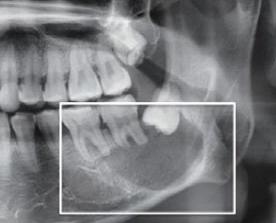

5、 阻生牙齿

当健康的牙齿遭到阻生牙齿的长期压迫,就会导致牙根部出现骨吸收,牙根也会跟着被腐蚀。一般这种情况多见于阻生智齿破坏健康邻牙牙根。